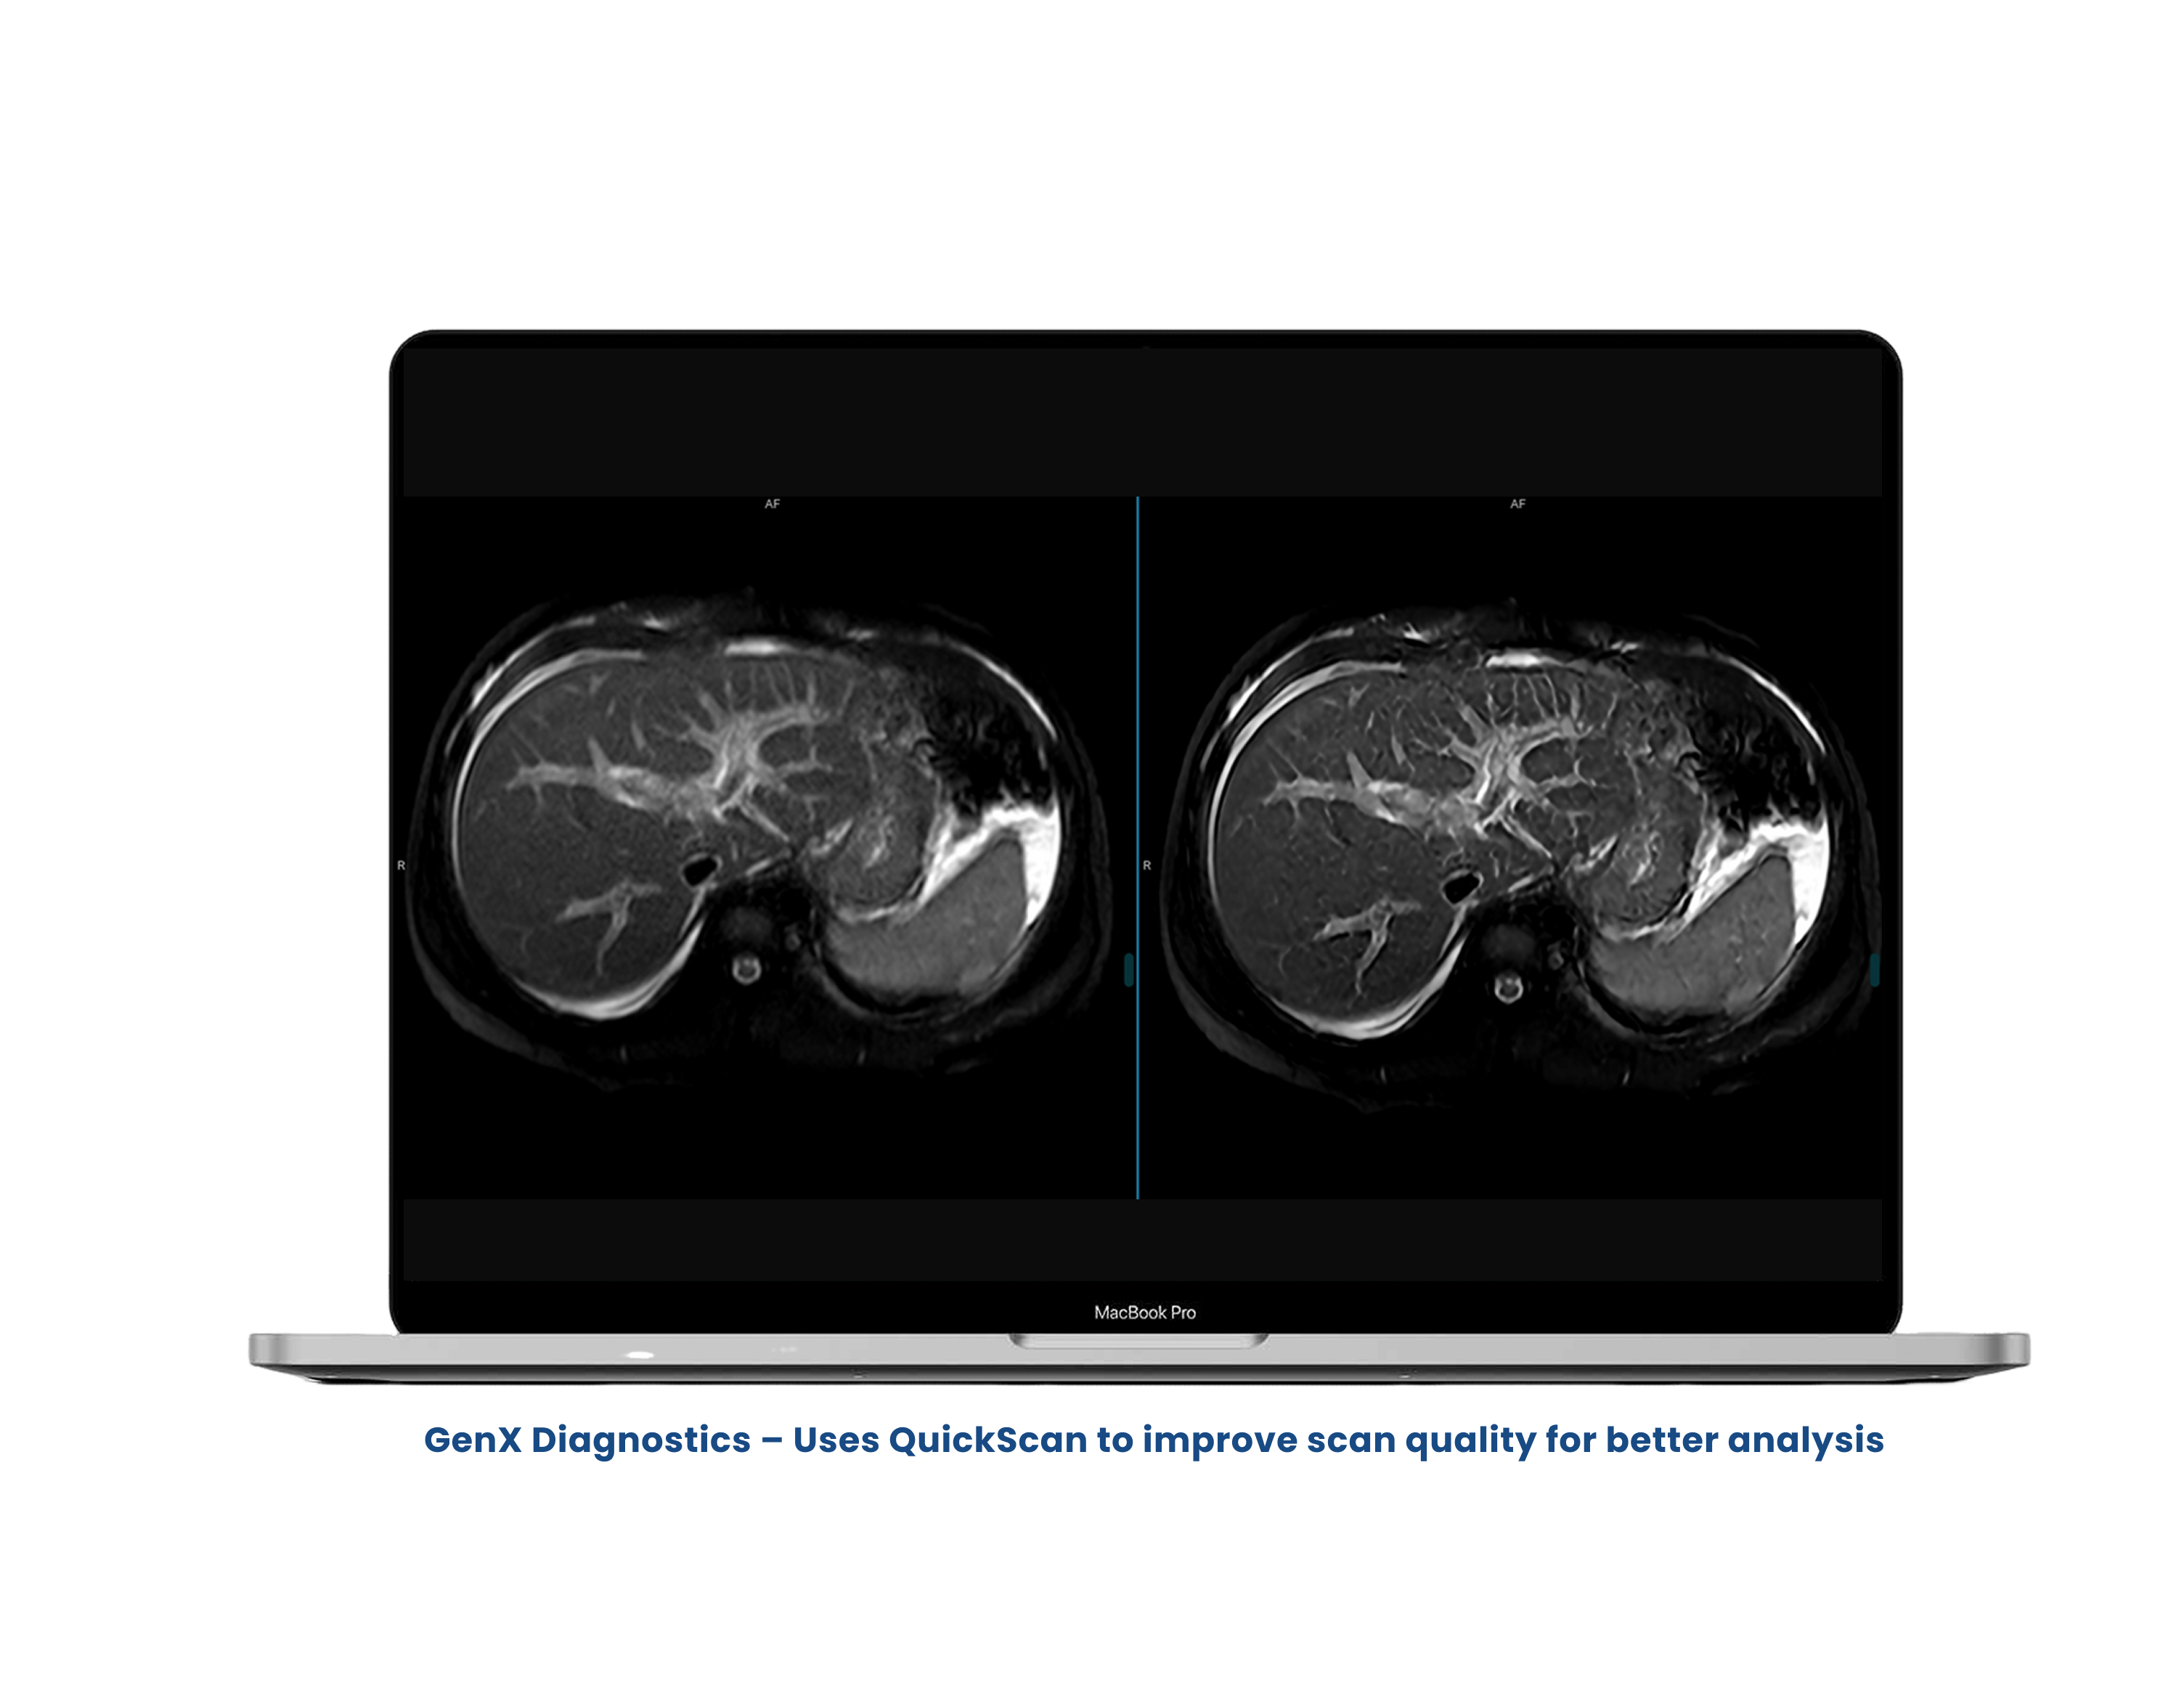

Improves Signal-to-Noise Ratio (SNR) using advanced AI reconstruction

Upgrades scan quality from older machines to match new systems